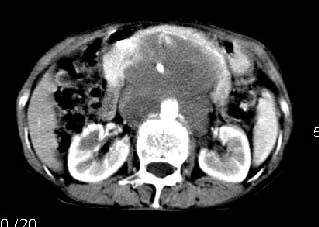

胰腺受压前移,胰管扩张,应为腹膜后占位,病灶密度不均,有低密度坏死区,强化扫描强化不明显腹腔干动脉受侵,考虑腹膜后恶性占位

从发病部位(腹主动脉周围)及增强方式(均匀轻度强化、少量坏死)和病变形态(较大、多结节形)符合腹膜后淋巴瘤,建议颈部病变活检。

我的第1诊断还是考虑是淋巴类病变1}。从病灶形态上看不是很规则,但其更向是多个结节的融和,其内有少许坏死,整个病灶的强化不是很明显,临近左恻肠间隔有增厚,2}我认为更重要的一点的是肠系膜有明显增厚呈片状。3}患者的脾脏不大其未见异常病灶。结合以上几点我首先考虑是转移性{但对此诊断我觉得不足之处;转移性的淋巴结肿大融合为什么没有坏死?}。{另外患者无大便习惯改变及血便,其发现右颈包块在今年过年无意发现}。以上是我的浅分析望各位战友继续讨论!谢谢!!

主动脉-胰腺间隙可见巨大分叶状软组织肿块影,包绕腹主动脉、腹腔干及其分支、腔静脉等大血管,增强呈无明显强化,临近脏器明显受压移位,增强示有分界。肝右叶可见局限性低密影,边缘清楚。

考虑腹膜后淋巴瘤。

影象表现:平扫,首先可见胃壁明显增厚,内外边缘清晰,外缘光滑,内边缘不归整,同时胃腔明显缩小。

再看从肠系膜根部到胰腺后主动脉及上腔静脉周围可见相连的较大的软组织肿块影,形态不规则,呈明显

的大小不等的分叶状,其中密度较均匀但其中可见条状低密度区,肿块边缘比较清晰周围的小肠受压移位

明显且堆积。

增强所见,腹腔动脉,肠系膜上动静脉被肿块包绕,结合平扫的条状低密度区恰好位于血管周围,较大的

肿块强化不明显(遗憾的是没有标上ct值)但胃壁强化的十分明显。